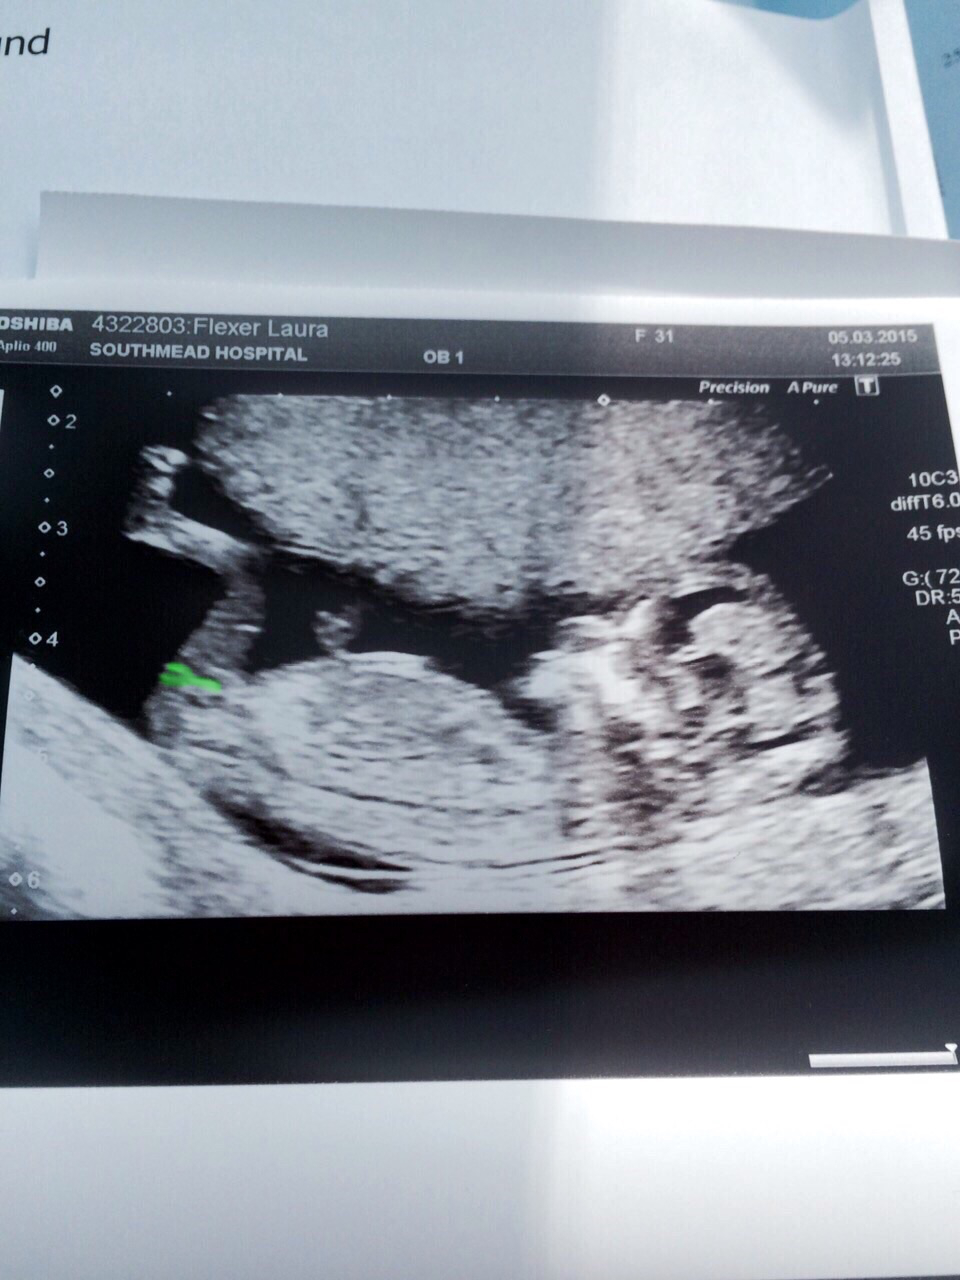

Hey all! Would be really grateful for your help! Having looked through hundreds of nub pics I'm sure there is a nub in front of the leg. I have seen many like it and people have commented on gender but on a few other sites most have said you can't see the nub. I would be most grateful for your opinion! Thank you! Pic is at 12+4 by scan but 11+5 by dates.